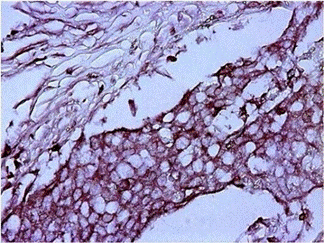

图2.福尔马林固定石蜡包埋组织的免疫组织化学染色。使用福尔马林固定石蜡包埋 (FFPE) 技术制备人结肠癌组织切片。为了暴露靶蛋白,使用 10 mM 柠檬酸钠 (pH 6.0) 缓冲液在 95°C 下进行热诱导抗原决定簇修复 20 分钟 抗原回收后,将组织置于室温 3% Thermo Scientific Blocker BSA (10X) 的 PBS 中 封闭 30 分钟,然后用 1 : 100 稀释的 Invitrogen Ezrin 单克隆抗体 (3C12) 进行 1 小时孵育。使用 Thermo Scientific Triton X-100 Surfact-Amps 去污剂溶液对组织进行充分洗涤 ,并使用 Thermo Scientific 过氧化物酶抑制剂 在室温下淬灭内源性过氧化物酶活性 30 分钟。使用 Invitrogen 山羊抗小鼠 IgG (H+L) HRP二抗 在 1 : 500 稀释度下进行检测,然后使用 Thermo Scientific 金属增强型 DAB 底物试剂盒进行比色检测。于40x的显微镜上成像。